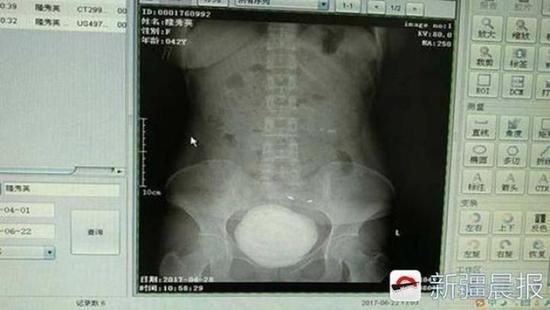

新疆晨报消息,近日,新疆阿克苏地区第一人民医院收治了一位结石患者。医生从患者隆女士的膀胱里取出来的结石,直径约10厘米,760克重,差不多赶上一个铅球大小,如此罕见的一个巨大结石,几乎撑满了隆女士的整个膀胱。

据阿克苏地区第一人民医院泌尿科主治医师刘峰介绍,当时患者隆女士来到医院拍片,腹部CT影像显示,结石占满膀胱,而且结石还有分层,像年轮一样。实际上,隆女士小时候就有结石了,但当时她一直没往这方面想,每次肚子疼时就吃点消炎药。